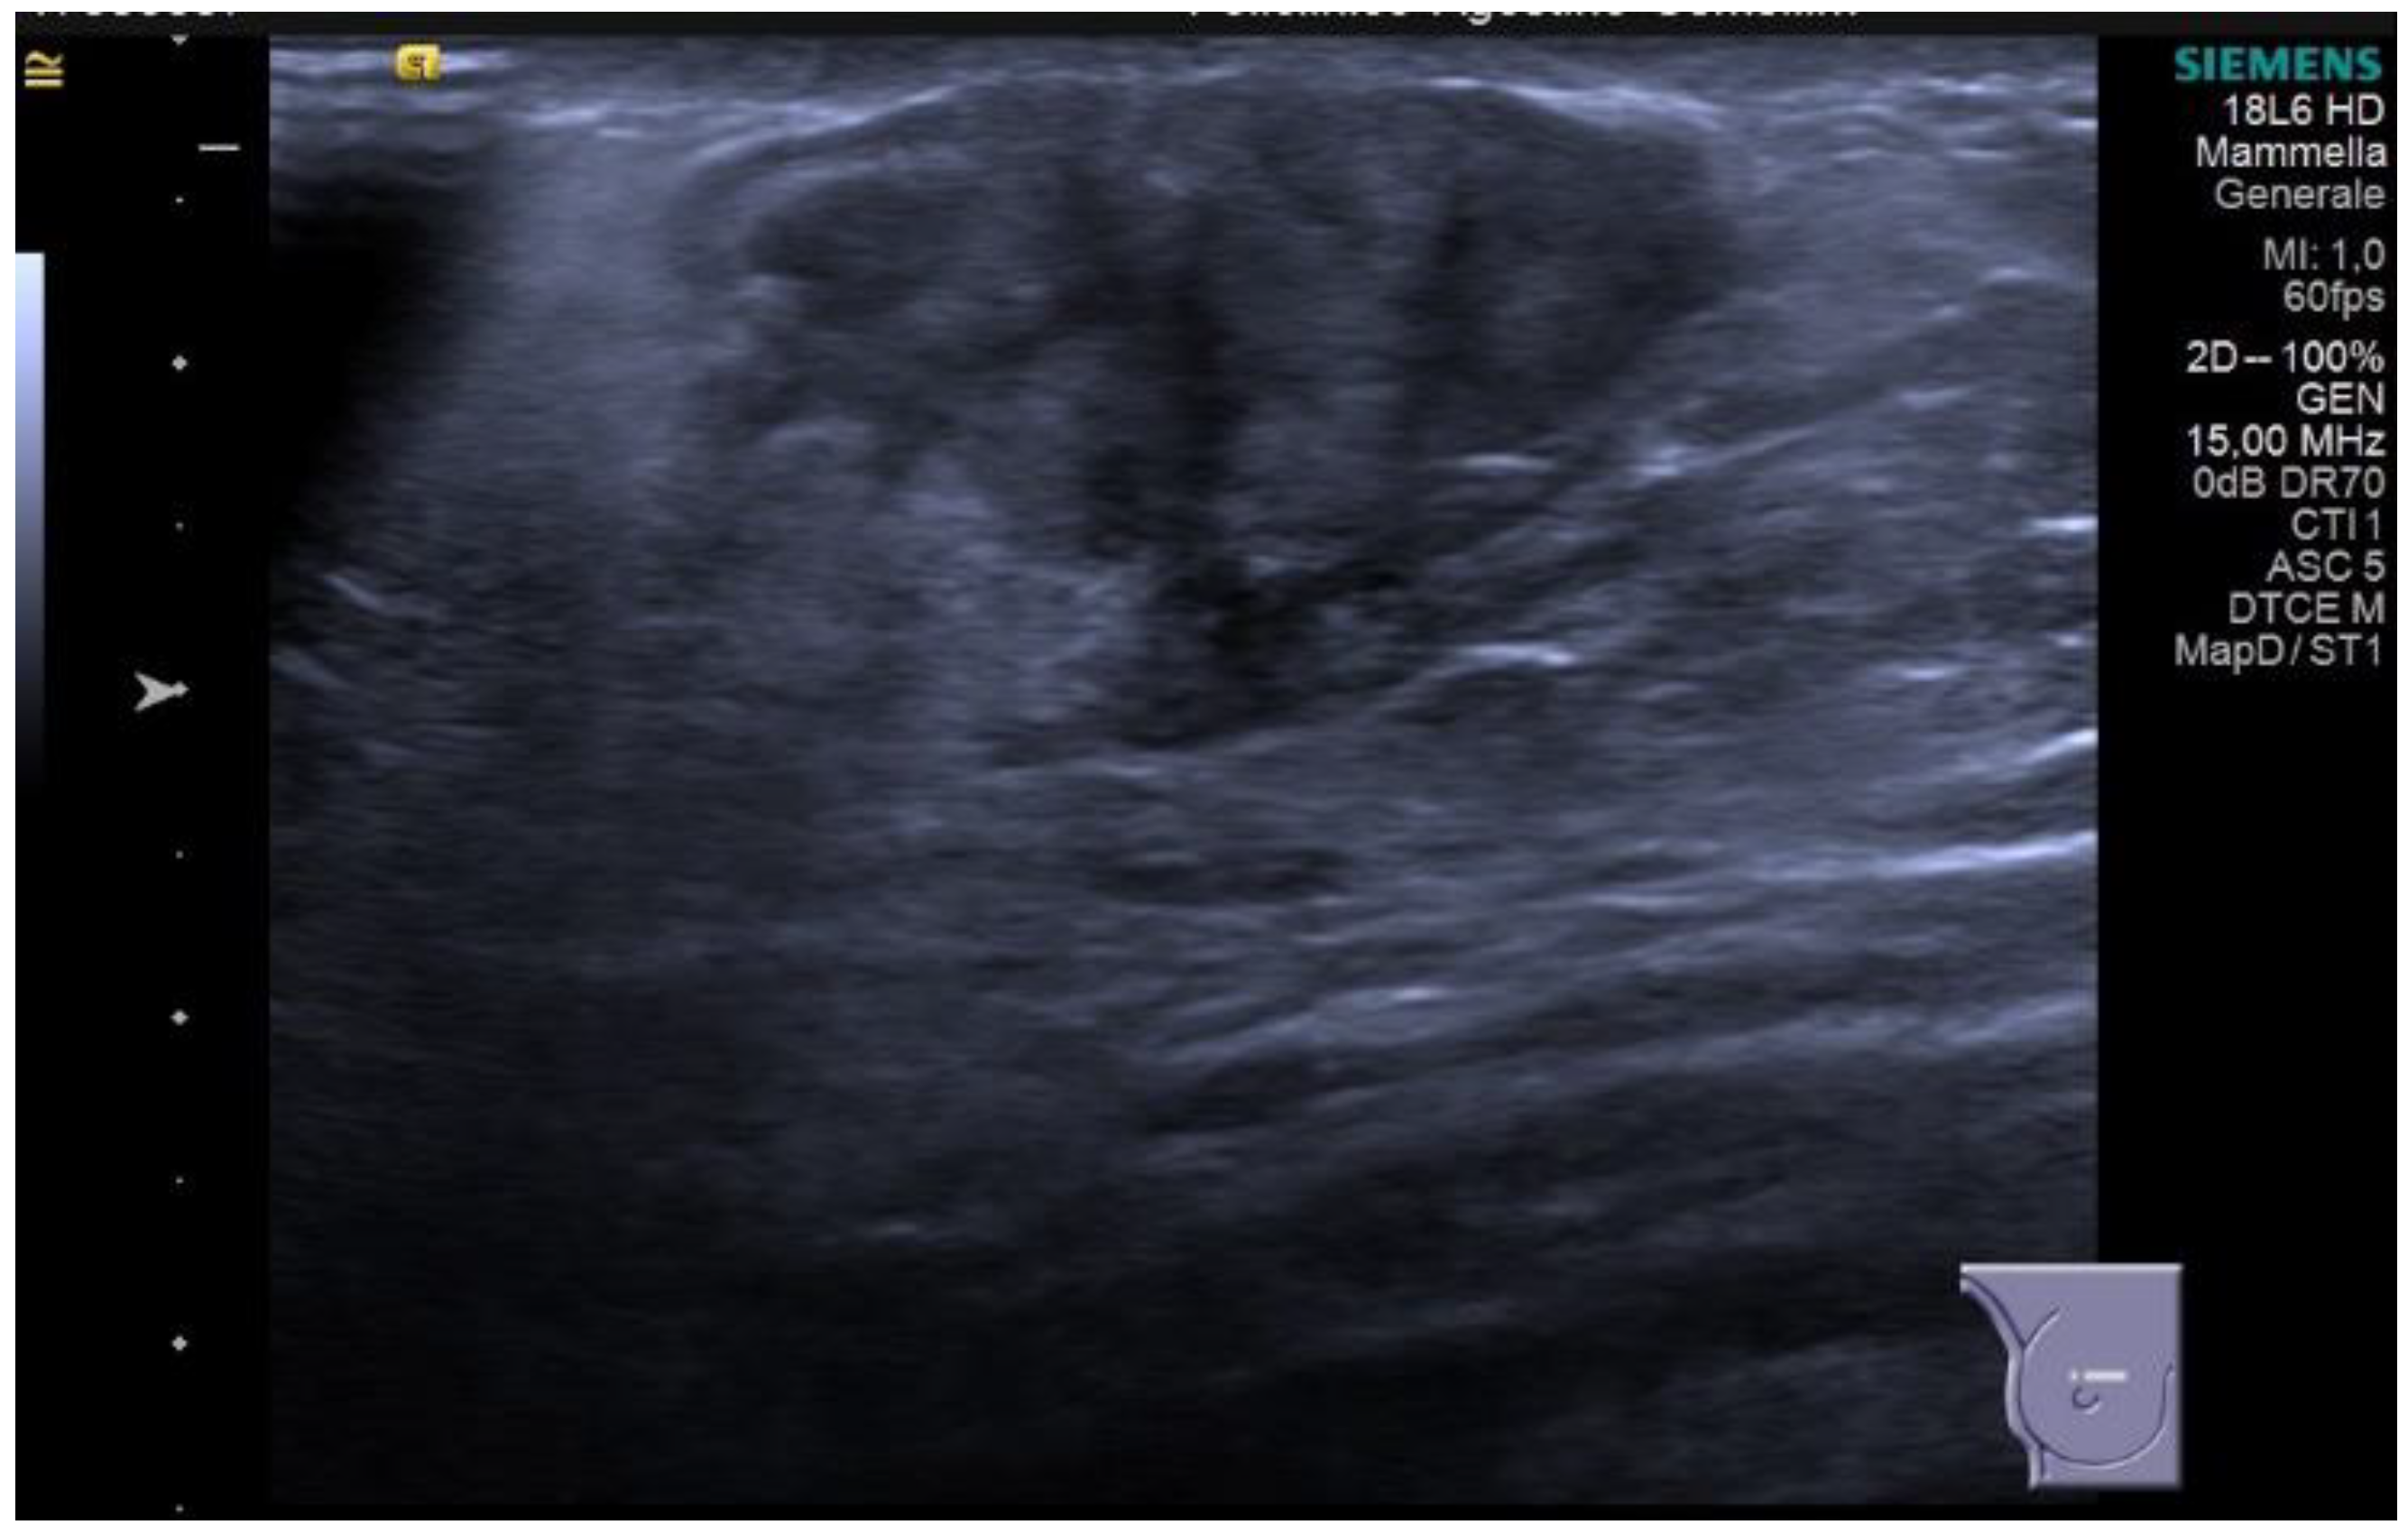

Diabetic mastopathy, although rare in men, is strongly associated with type 1 diabetes. It may present as single or multiple lesions in the breast, and imaging findings can mimic malignancy. Mammographically, it can appear as an ill-defined solid mass, architectural distortion, or asymmetric densities. Ultrasonography reveals an irregular hypoechoic mass with posterior acoustic shadowing and internal vascularization (Figure 5).

Figure 5.

Palpable lump on the right side in a 71-year-old man, with a personal history of type 1 diabetes and hypertension. On breast ultrasound, there is a subareolar irregular shaped and hypoechoic mass, with not-circumscribed margins and vertical orientation. No posterior feature is associated. The mass is suspicious for malignancy (BI-RADS 4b) and a core-needle biopsy was performed. Final histology: fibrosis, gynecomastia, and chronic inflammation are consistent with diabetic mastopathy.

However, in some cases, diabetic mastopathy may appear as well-circumscribed masses without associated posterior features or vascularization, suggesting a benign nature [18,19].